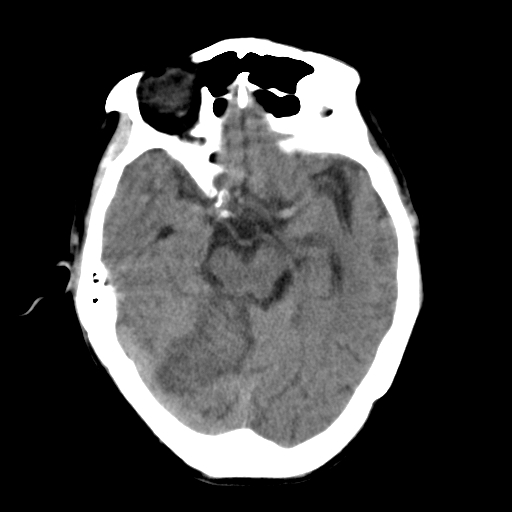

标题: CT25306:男性,75岁。右侧肢体无力一周。 [打印本页]

标题: CT25306:男性,75岁。右侧肢体无力一周。

右侧小脑楔形片状低密度影,考虑脑梗塞,建议mri或增强检查除外肿瘤占位

1)右侧小脑梗塞。2)脑萎缩。